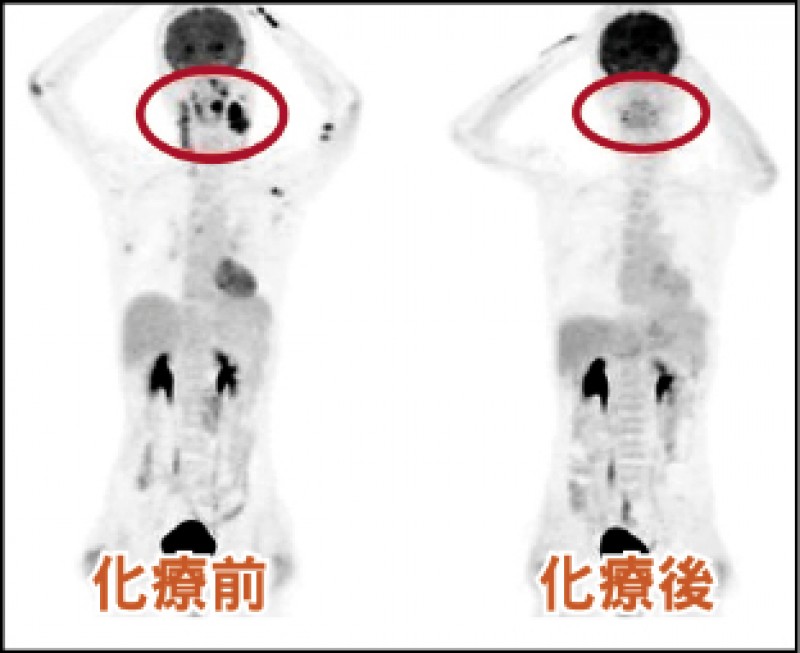

34歲的朱先生,去年底摸到左頸有腫塊,原以為只是感冒引起,但感冒痊癒後,腫塊卻持續變大,趕緊赴醫求診,經切片檢查,確診為「瀰漫型大B細胞淋巴癌」第3期,嚇得他六神無主。所幸經醫師建議接受標靶藥物及化療後,病情獲得控制,醫師建議,如發現身體有不明腫塊應及早就醫檢查,以免延誤治療。

黃文豊說,淋巴癌分期通常以橫膈膜為,朱先生因橫膈膜兩側皆受到癌細胞侵犯,判定為淋巴癌第3期,治療方式包括放射線治療、化學治療、標靶治療等,若初期治療效果不佳或癌症復發時,會使用高劑量化學治療合併自體或異體周邊血幹細胞移植。

標靶藥物+化療 病情獲控制

「瀰漫型大B細胞淋巴癌」第3期的5年存活率約30%到50%,但化學治療效果好,同時大多數60歲以下患者不會出現太多化療副作用,若再搭配標靶藥物治療,通常能達到不錯的療效。